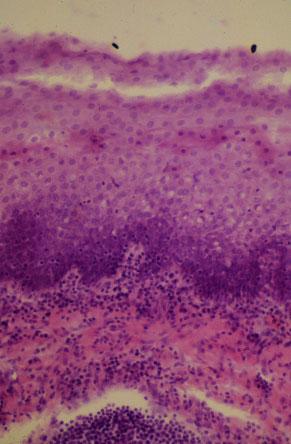

VI-61 (4) Slide 38, Palatine Tonsil (H&E). Strati-fied squamous nonkeratinizing epithelium is invaded by lymphocytes.